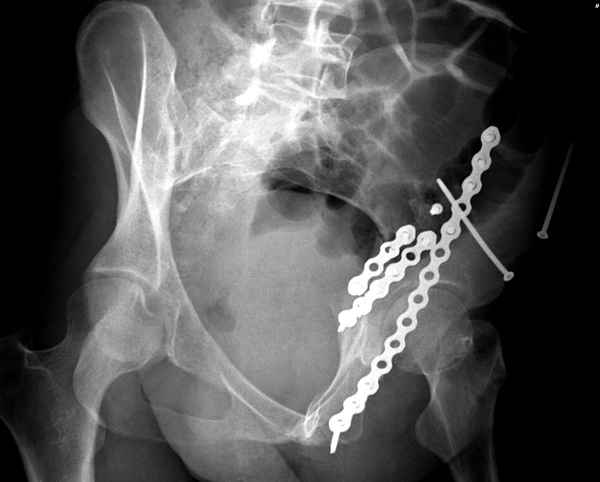

Все выступающие коллеги высказались насчет необходимости стандартных снимков по Judet, потому что для определения тактики лечения переломов вертлужной впадины 3Д снимки малоинформативны.

Летурнель разработал классификсацию на основании прямого, запирательного и подвздошного рентген снимков, котоые, кроме описания характера переломов, также подсказывают адекватный доступ для репозиции перелома.

Из того минимума, что представлено, мне кажется, мы имеем дело с двухколонным переломом вертлужной впадины. Обычно медиальный (центральный) "вывих" головки встречаются в сложных двухколонных переломах со смещением.

По-моему, надо готовить больного к будущей артропластике, но без опоры на задний столб невозможно удержать протез. Опорная конструкция (кольца и т.д.) должны иметь опору, и поэтому мы бы сделали реостеосинтез задним доступом. При надобности остеотомия и рутинная фиксация с межколонными винтами.

Здесь несколько вариантов двухколонных свежих переломов, которые были оперированы из одного-заднего, а также из двух: переднего и заднего доступов.